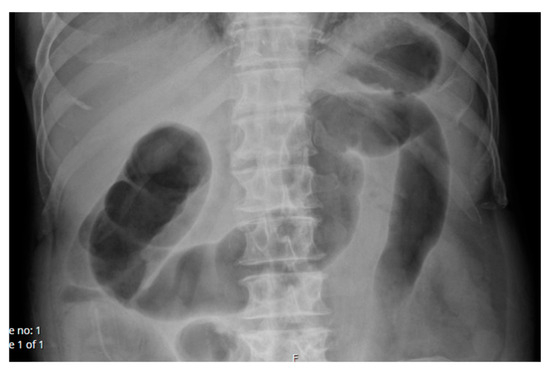

2.1.2. Case 2